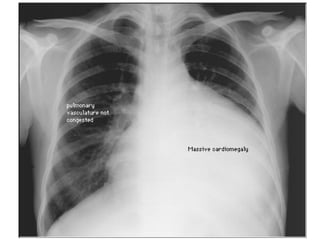

CXR- globular heart Describe? Large globular heart Massive cardiomegaly Causes? Pericardial effusion Cardiac tamponade Dilated cardiomyopathy Severe ASD Other Ix? ECG (axis? low voltage?) Echo/TEE

CXR- globular heartDescribe? Large globular heart Massive cardiomegaly Causes? Pericardial effusion Cardiac tamponade Dilated cardiomyopathy Severe ASD Other Ix? ECG (axis? low voltage?) Echo/TEE